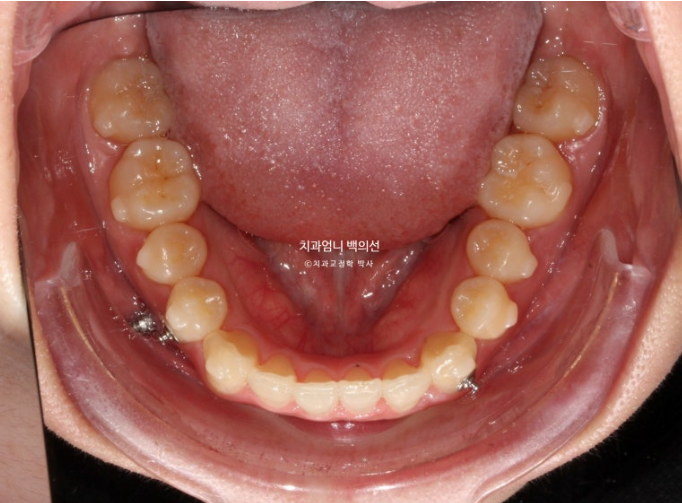

23.07

23년 7월 교정치료를 위해 내원한 환자분입니다.

고치고 싶은 것은 중심선 비대칭과 덧니입니다.

왼쪽 위 작은어금니 하나가 선천적으로 없으면 이로 인해 그쪽으로 윗니 중심선이 돌아가 있습니다.

다른 병원 상담에서는 결손된 작은어금니를 제외한 나머지 작은어금니 3개를 발치해야 하고 치료기간은 2년 이상 소요된다고 듣고 오셨습니다.

앞니가 뻗쳐 있습니다.

파란 화살표가 원래 작은어금니가 하나 더 있어야할 자리, 즉 선천적으로 결손된 작은어금니 자리입니다.

다행인건 가용한 사랑니 공간이 충분한 점입니다.

입매 돌출감이 미미하여 비발치 치료 권유드렸습니다.

즉 작은어금니 발치 없이 사랑니 공간을 이용하여 교합을 맞추고 중심선을 맞추기로 했습니다.